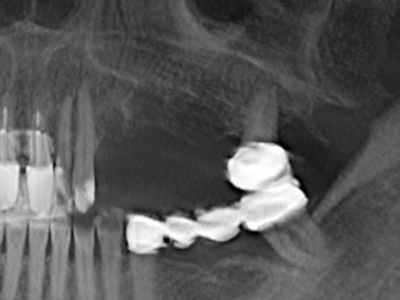

When surgical procedures are performed on bone in the immediate vicinity of sensitive structures such as blood vessels or nerves, rotary instruments pose a significant risk of iatrogenic injury. Piezoelectric devices can be helpful for preparation of bone covers and removal of hard tissue close to nerves, particularly for exposure of nerves after iatrogenic injury but also during nerve lateralization for resective and reconstructive procedures or implant placement (Fig. 17-20). Light contact between the piezotip and the nerve does not generally result in damage but proceeding incautiously with saw-like motions or attachments where a residual bone substrate remains may cause temporary or even permanent nerve damage. However, the risk of damage is considered to be substantially lower than when using saws or milling instruments (Pereira, Gealh et al. 2014).